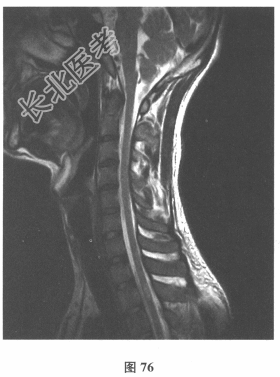

颅脑MRI:无异常。血清AQP-4抗体(-),脑脊液OB(+),各种自身抗体测定均阴性。VEP:右眼P100潜伏期延长。患者3年前无明显诱因出现双下肢麻木无力,伴有大小便障碍,脊髓MRI显示髓内长T₂信号影,见图76、图77。)此患者的诊断考虑